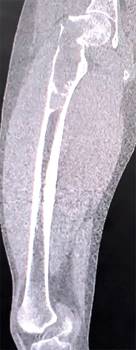

Se realizaron radiografías de pelvis y de fémur, que revelaron una fractura basicervical de fémur derecho Garden II Pauwells III AO 31B2.3r, con un patrón lítico de destrucción geográfica y un margen esclerótico bien delimitado que se extendía hacia el fémur distal aproximadamente 14 cm, sin evidencia de reacción endóstica o perióstica (Figura 1). Estas imágenes eran compatibles con una lesión de lento crecimiento, que necesitaba confirmación mediante histopatología, ya que, como se mencionó previamente, a pesar de que el paciente cuenta con antecedente de DF, existen otras entidades, algunas de comportamiento biológico maligno, de las cuales debe hacerse diagnóstico diferencial. Como estudio complementario, se realizó una tomografía simple de fémur derecho, ya que nos permite delimitar perfectamente los bordes de la tumoración para la planeación quirúrgica, así como precisar el patrón de destrucción lítico y el adelgazamiento del hueso cortical (Figura 2). Los parámetros del metabolismo óseo se encontraban dentro de valores normales.

Figura 2: Tomografía computarizada simple de todo el fémur derecho en una proyección coronal donde puede delimitarse el borde distal de la tumoración ósea, así como el adelgazamiento cortical proximal.